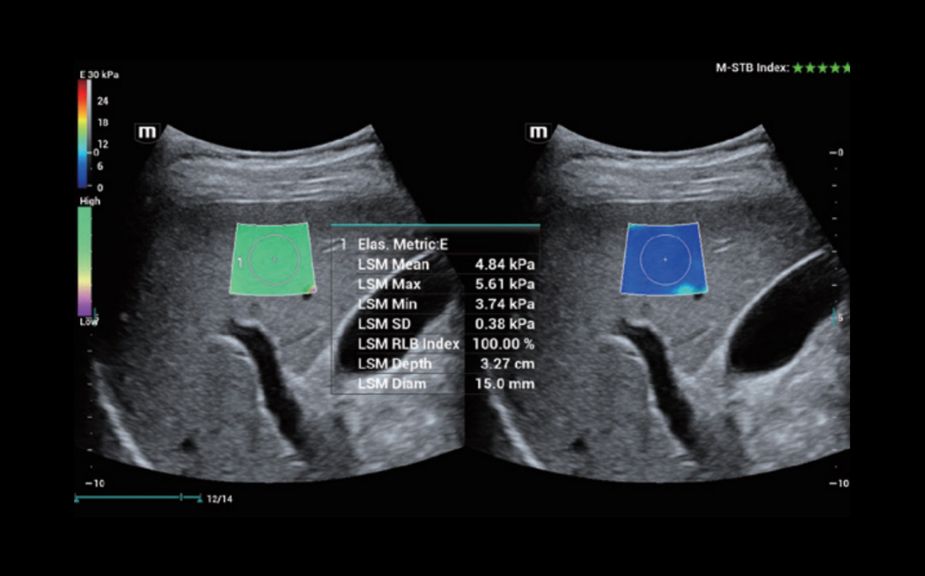

–ė–Ĺ–Ĺ–ĺ–≤–į—Ü–ł–ĺ–Ĺ–Ĺ–į—Ź –ĺ—Ü–Ķ–Ĺ–ļ–į –∂–Ķ—Ā—ā–ļ–ĺ—Ā—ā–ł: HiFR STE

–í 10 —Ä–į–∑ –Ī–ĺ–Ľ–Ķ–Ķ –≤—č—Ā–ĺ–ļ–į—Ź —á–į—Ā—ā–ĺ—ā–į –ļ–į–ī—Ä–ĺ–≤ –Ņ—Ä–ł —Ä–į–Ī–ĺ—ā–Ķ —Ä–Ķ–∂–ł–ľ–į STE

–í—č—Ā–ĺ–ļ–į—Ź —á—É–≤—Ā—ā–≤–ł—ā–Ķ–Ľ—Ć–Ĺ–ĺ—Ā—ā—Ć –ļ –ī–≤–ł–∂–Ķ–Ĺ–ł—é –ī–Ľ—Ź –Ņ–ĺ–≤—č—ą–Ķ–Ĺ–ł—Ź —Ā—ā–į–Ī–ł–Ľ—Ć–Ĺ–ĺ—Ā—ā–ł –ł —ā–ĺ—á–Ĺ–ĺ—Ā—ā–ł

HiFR STE –Ĺ–ĺ–≤–ĺ–ĺ–Ī—Ä–į–∑–ĺ–≤–į–Ĺ–ł—Ź –ľ–ĺ–Ľ–ĺ—á–Ĺ–ĺ–Ļ –∂–Ķ–Ľ–Ķ–∑—č

HiFR STE –Ņ–Ķ—á–Ķ–Ĺ–ł

–ė–Ĺ–Ĺ–ĺ–≤–į—Ü–ł–ĺ–Ĺ–Ĺ–į—Ź –ĺ—Ü–Ķ–Ĺ–ļ–į –∂–Ķ—Ā—ā–ļ–ĺ—Ā—ā–ł: HiFR STE

–í 10 —Ä–į–∑ –Ī–ĺ–Ľ–Ķ–Ķ –≤—č—Ā–ĺ–ļ–į—Ź —á–į—Ā—ā–ĺ—ā–į –ļ–į–ī—Ä–ĺ–≤ –Ņ—Ä–ł —Ä–į–Ī–ĺ—ā–Ķ —Ä–Ķ–∂–ł–ľ–į STE

–í—č—Ā–ĺ–ļ–į—Ź —á—É–≤—Ā—ā–≤–ł—ā–Ķ–Ľ—Ć–Ĺ–ĺ—Ā—ā—Ć –ļ –ī–≤–ł–∂–Ķ–Ĺ–ł—é –ī–Ľ—Ź –Ņ–ĺ–≤—č—ą–Ķ–Ĺ–ł—Ź —Ā—ā–į–Ī–ł–Ľ—Ć–Ĺ–ĺ—Ā—ā–ł –ł —ā–ĺ—á–Ĺ–ĺ—Ā—ā–ł

HiFR STE –Ĺ–ĺ–≤–ĺ–ĺ–Ī—Ä–į–∑–ĺ–≤–į–Ĺ–ł—Ź –ľ–ĺ–Ľ–ĺ—á–Ĺ–ĺ–Ļ –∂–Ķ–Ľ–Ķ–∑—č

HiFR STE –Ņ–Ķ—á–Ķ–Ĺ–ł